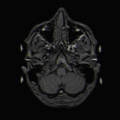

After concluding that syntax and semantics were separate from one another, Friederici et al (2003) used functional magnetic resonance imaging (fMRI) to try and localize the areas involved. fMRI analysis localized the N400 ERP from semantic processing within the brain: the hippocampus may be involved, cortical areas within the superior temporal sulcus, and the left auditory cortex. When using fMRI to analyze the ELAN involved in syntactic processing it was found that the ELAN was localized within the anterior temporal and inferior frontal cortices in both hemispheres, but there was left hemisphere dominance. Friederici et al (2003) designed an experiment using anomalous sentences (abnormal sentences) in order to localize the regions involved in the P600. Friederici et al's (2003) study did identify that the left basal ganglia of the putamen was associated with the P600 potential. It was found to be involved in the later controlled syntactic processing rather than with the early structure building processes. This study did show that there was a difference between semantic and syntactic processing, as well showed the different regions within the brain associated with the two ERPs involved in syntactic processing. Latter studies found that in patients who had neuro-debilitating diseases like Parkinson's disease had a reduced P600 potential as a result of impaired basal ganglia.

Early researchers theorized that semantics and syntax involved in Wernicke's and Broca's area and thus they wanted to localize semantics and syntax processing onto these areas respectively.[9] Technologies such as electroencephalography (EEG), magnetoencephalography (MEG), and functional magnetic resonance imaging (fMRI) studies revealed that there were inconsistencies with this theory. Grodzinsky and Friederici (2006) examined previous research results that used MEG, fMRI, and EEG technologies and attempted to localize syntactic processing using previous results.

Grodinzsky and Friederici found that the frontal operculum, which is in the left inferior frontal gyrus and is adjacent to the inferior region of Broca’s area, was involved in understanding phrase structures. They also found that the anterior superior temporal gyrus was involved in processing structure violations, and it appeared that it was recruited in order to identify mismatching between the incoming sentence and the expected syntactic structure of the sentence. MEG studies revealed that these two structures were involved in local phase structure building but it appeared that the largest activation came from the left anterior super temporal gyrus, while a smaller activation was seen in the inferior frontal cortex.

Grodzinsky and Friederici saw that when sentences had complex syntax, there was an activation with Broca’s area (Brodmann’s area 44, 45) and they concluded that this activation was due to an increase on the working memory. This was confirmed through electrophysiological data. When integrating syntactic information, the left posterior superior temporal gyrus became active. Grodzinsky and Friederici theorized that this region was most likely used to support the integration of syntactic and lexical information between the left and right posterior superior temporal gyrus. This was supported through ERP measurements, with the discovery of a late centro-parietal positivity that occurred 600 ms (P600) after being presented with information.

The most important thing that Grodzinsky and Friederici concluded was that syntax processing actually occurred within the left interior frontal gyrus (IFG) and not Broca's area. Not only is the IFG responsible for syntax processing but other subdivisions are involved in different stages of syntax processing. See areas in syntax processing for further information.